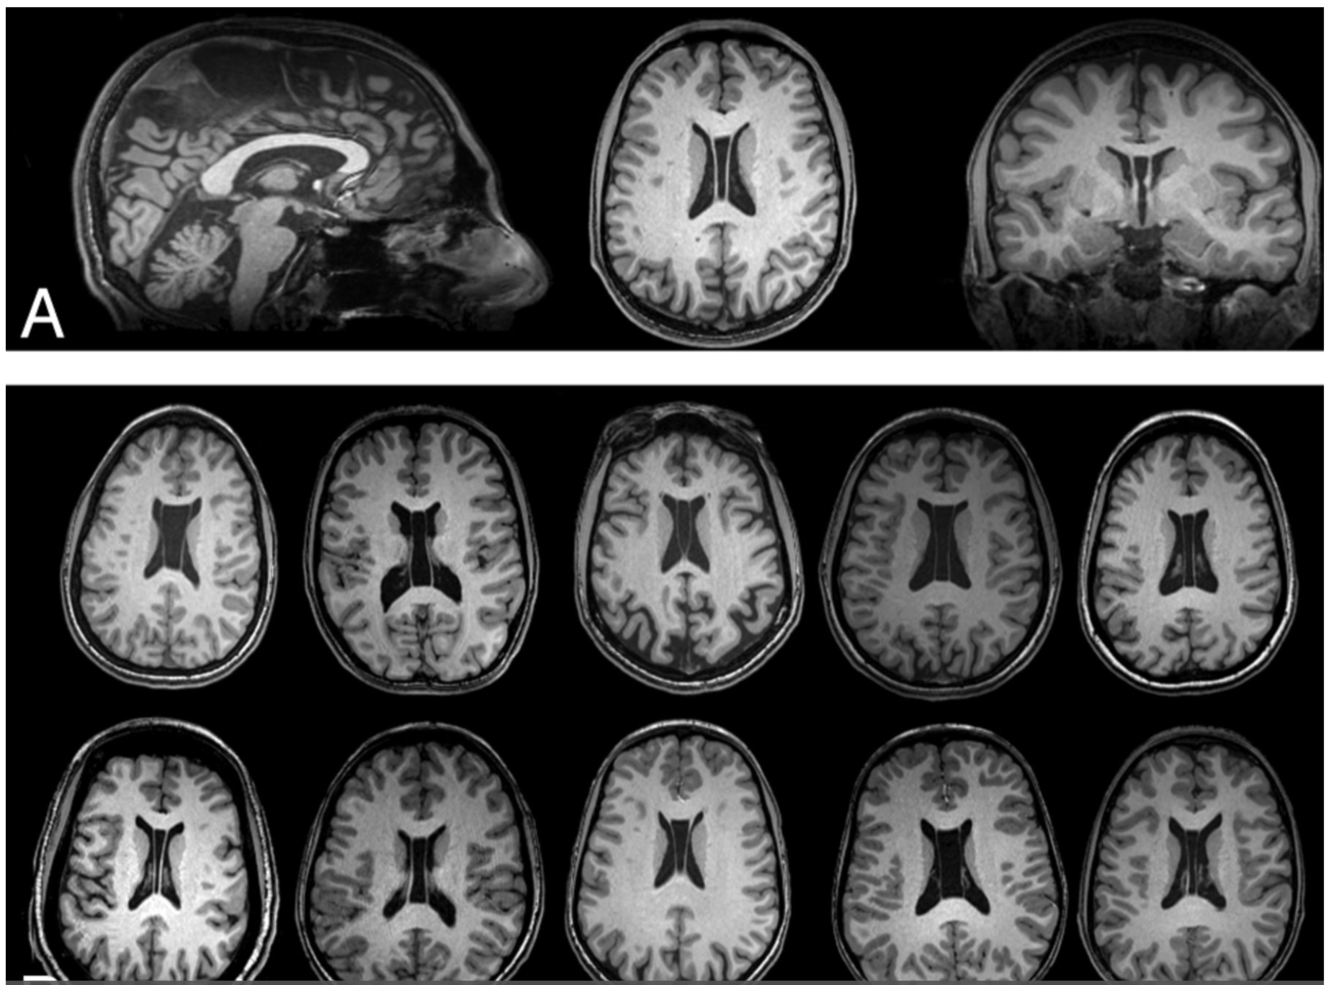

What syndrome is this finding associated with

http://www.ajnr.org/content/35/11/2186

Di George

CATCH22

C - cavum septum pelucidum, cleft palate,

A - Abnormal Facies (hypertelorism, low set ears, short philtrum, among others)

T - Trunchus ateriosus, Thymic Hypoplasia

C - cardiac anomalies

H - hearing problems. Middle ear malformations. Hypoparathyroidism

22 - Microdeletion of 22q11.2

Lack of Myelination in the Anterior Limbs of the Internal Capsule Associated with Cri-du-Chat Syndrome: Case Report

H. Lee, S. You, +1 author Hyun-Hae Cho

Published 2015

Medicine

Investigative Magnetic Resonance Imaging

A 21-month-old girl with cri-du-chat syndrome in conjunction with developmental delay underwent brain magnetic resonance imaging (MRI). The MRI showed hypoplasia of the brain stem, a normal cerebellum, thinning of the corpus callosum, and a lack of myelination in both anterior limbs of the internal capsule. She also had neonatal bilateral subependymal cysts. We believe that the symmetrical lack of myelination in both anterior limbs of the internal capsule could be a diagnostic clue of cri-du-chat syndrome. LESS